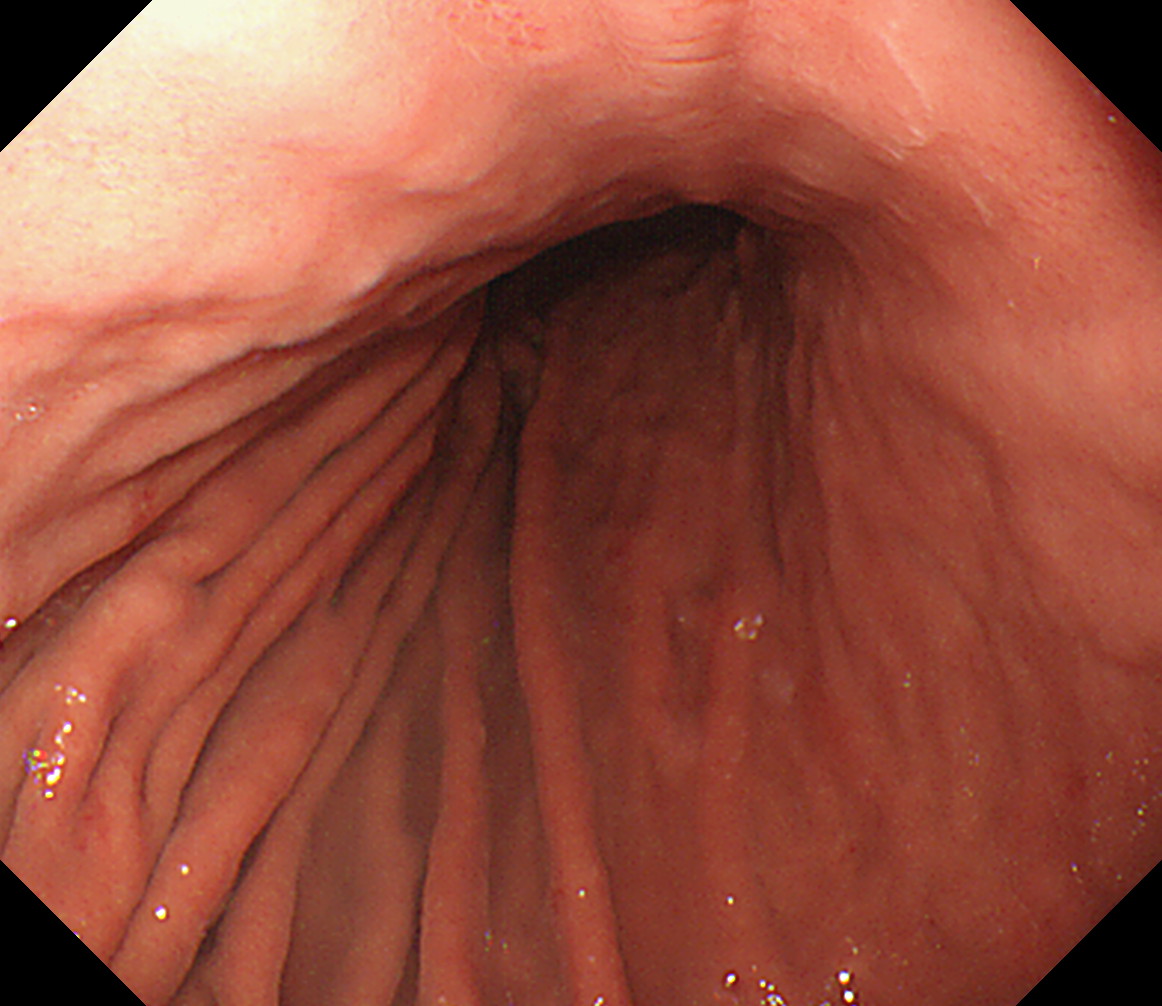

10 十二指腸球部後壁 この後十二指腸下降脚とVater乳頭を観察します 中部食道

11 胃角部後壁 [見下ろし]になります 中部食道

12 胃角部小弯 [J反転]見上げになります 胃角部後壁

13 胃角部前壁 再度、[見下ろし]になります 胃角部前壁